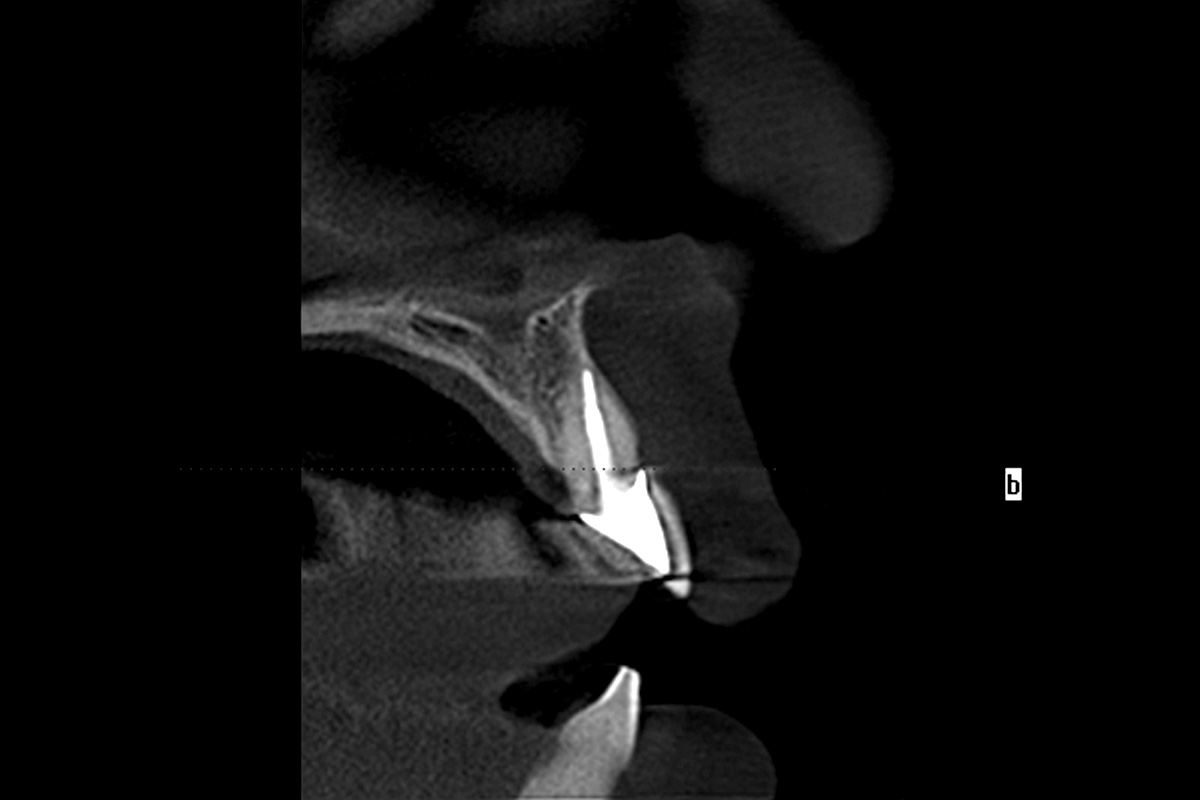

cerabone® and mucoderm® for immediate implantation in the aesthetic area - Dr. D. Robles

Initial clinical situation - Central incisors with dental destruction and periapical pathology